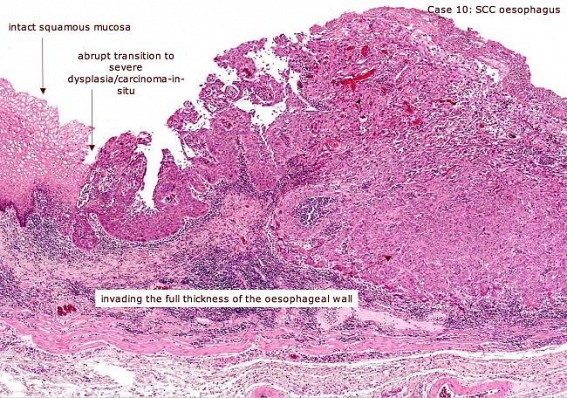

PHOTO : Carcinoma of the Oesophagus. Picture source : Internet

A tea garden labour-sardar, Kenaram Munda was admitted with history of increasing Dysphagia (difficulty in swallowing).After admission I had passed an the Oesophagoscope to confirm that he had cancer of the esophagus in the middle third-biopsy , histology confirmed that it was Columner cell Carcinoma”, of the middle third of esophagus. Kenaram was a heavy smoker and an alcoholic, but a pleasant man. We became friends.

It is the 6th commonest malignancy in humans, after 50th year of age, is a morbid disease with a grim prognosis, has a tendency of Occult metastasis (cause of large percentage of failures) now detectable by Positron emission tomography(PET) test which makes it possible to detect a spread, not possible to detect otherwise. A growth remains symptom less till 2/3 of the lumen is obliterated, so detection is nearly always late and post operative results get poorer with lost time .It is common among Alcohol and tobacco abusers and follow usually Reflux oesopagitis or Barrett’s oesophagitis.